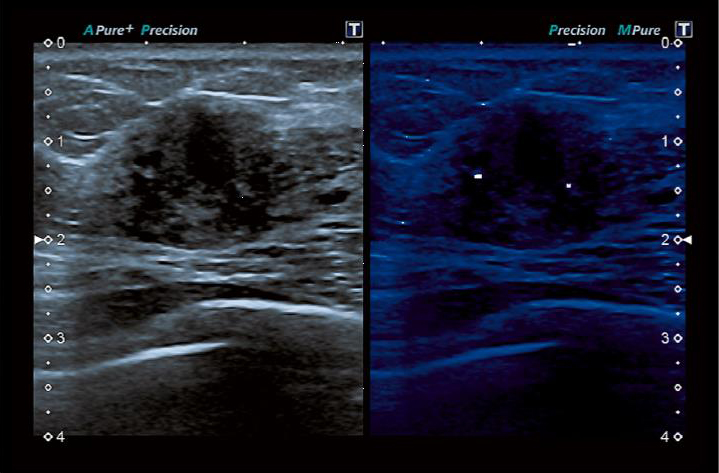

MicroPure 기능으로 유방암 진단에 중요한 미세석회병변을 확인할 수 있습니다.